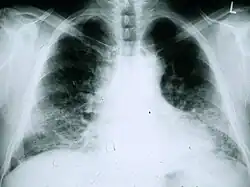

Chest X-rays are useful in the follow-up routine of IPF patients. Plain chest X-rays are unfortunately not diagnostic but may reveal decreased lung volumes, typically with prominent reticular interstitial markings near the lung bases.[3]

A chest radiograph of a patient with IPF. Note the small lung fields and peripheral pattern of reticulonodular opacification.